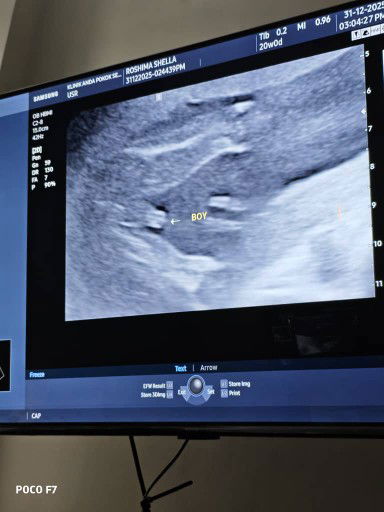

USG 20 weeks due may 2026

USG 20 weeks. nampak boy. agak2 betul tak boy...haha... 23 week ni nk buat anatomy scan plak... ada tak sini yg scan boy tp keluar girl?#firsttimepreggy